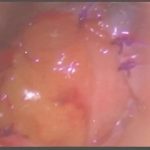

術中写真

摘出 後